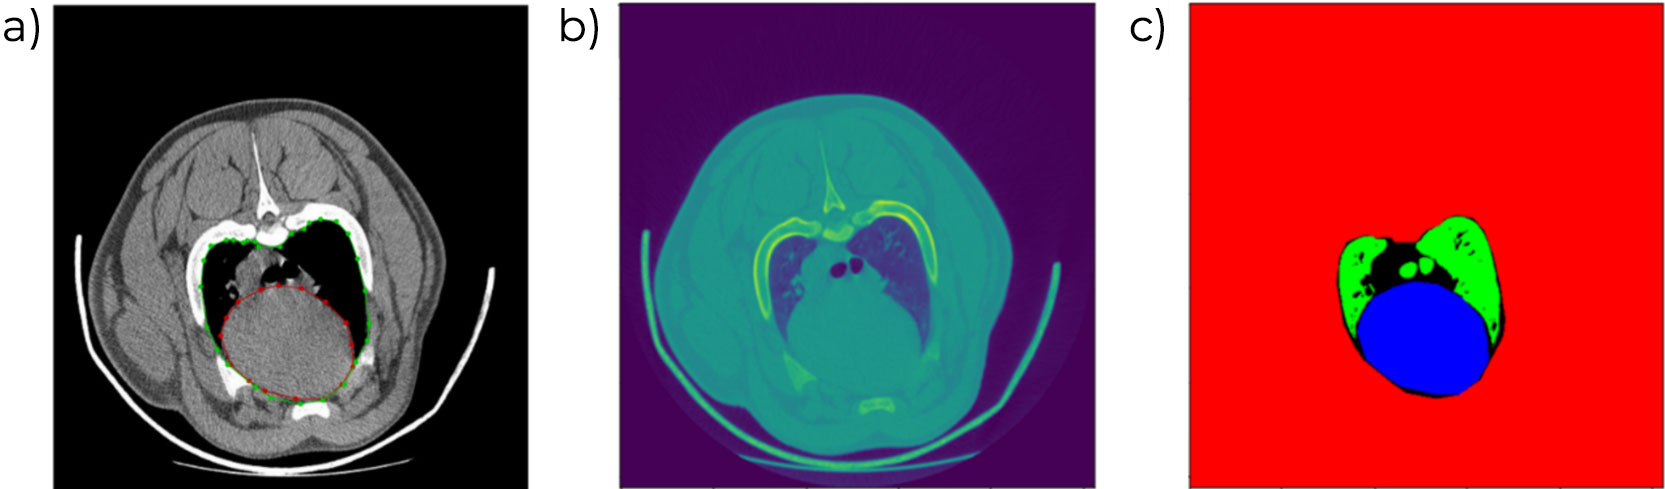

Obecność zmian chorobowych w głowie kości udowej i ramiennej w celu zidentyfikowania procesów zapalenia stawów lub osteochondrozy. Ocena ta stanowi część celu selekcji dla wszystkich linii genetycznych. Proces oceny obejmuje element manualny, który wkrótce zostanie zastąpiony zautomatyzowanym procesem segmentacji i kwantyfikacji zmian chorobowych, co pozwoli również na ocenę większej powierzchni kości.